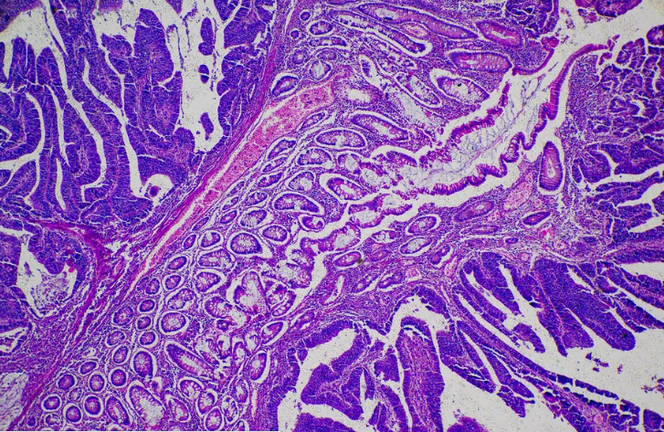

Dostarlimab, một loại kháng thể đơn dòng đang khiến giới y học xôn xao về hiệu quả của nó. Trong thử nghiệm của Trung tâm Ung thư Memorial Sloan Kettering (Mỹ), tất cả 12 bệnh nhân ung thư trực tràng sử dụng thuốc này được chữa khỏi hoàn toàn.

Trước Dostarlimab, từng có nhiều nghiên cứu về thuốc trị ung thư nhưng không ứng viên nào đạt hiệu quả 100% như loại thuốc này.